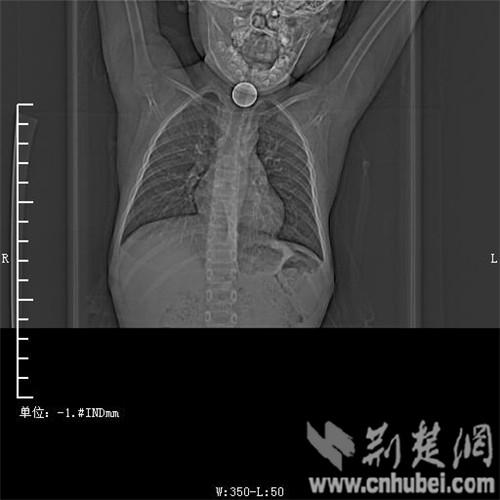

圖為:硬幣卡在了陽陽的喉部

消化內主任方向明告訴記者,孩子送來時已經是晚上8點15分,醫(yī)護人員立即給孩子拍胸部CT確定硬幣的位置,8點30分,方向明通過胃鏡下食管異物取出術,成功的將這枚一元硬幣取了出來。1月5日上午,陽陽順利出院,醫(yī)生護士在他出院時不斷告訴他,以后千萬不要吞含異物。